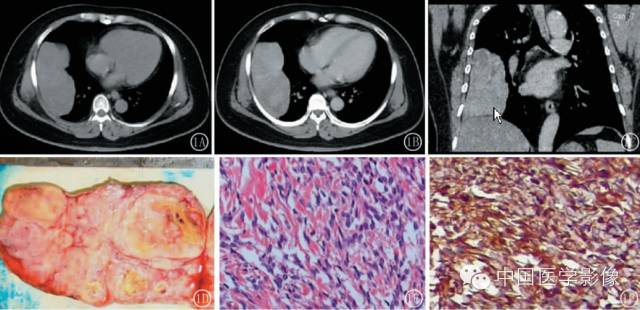

病理

SFT大体标本一般表现为:包膜完整,质地坚韧,切面呈灰白色或灰红色,部分可见致密黄色脂肪组织。HE镜下表现形态多样,无一致的排列模式被描述为无特征构像,但仍具有以下特点:肿瘤细胞大小较一致,胞质含量少,核染色质均匀分布,细胞排列无一定模式,肿瘤细胞与嗜酸性胶原混杂排列,肿瘤细胞呈束状或散乱排列成细胞密集区和细胞疏松区,前者胶原较少呈小簇状或网状穿插于细胞间,后者胶原丰富呈粗带状,并可形成瘢痕疙瘩样的密集胶原束。肿瘤中血管较丰富并可形成典型的血管外皮瘤样区。SFT免疫组织化学特点为CD34阳性,其对于SFT的鉴别诊断很有价值,但CD34阳性并非SFT所特有故确诊SFT除依靠免疫组织化学外必须具备光镜下多样化的组织学形态及特征。

1.外形及囊变坏死:良性SFT一般为边界清晰的单发肿块无分叶或浅分叶,肿瘤大多呈实性,囊变坏死区较小。恶性SFT一般为囊实性或囊性为主肿块呈分叶状坏死范围广泛。

2.密度或信号特点:肿瘤实性部分CT表现为软组织密度,囊变坏死区呈低密度。位于胸腔的SFT尽管体积巨大,但密度相对均匀,坏死少见且范围多较小。良性肿瘤坏死少见,恶性肿瘤不规则坏死区相对多见。腹部SFT都有不同程度的坏死囊变和钙化。MRI除了能够提供明确肿瘤的确切部位及累及范围外,对于明确肿瘤的组成成分具有重要价值。MR信号改变与肿瘤的组织学特征密切相关,其内成熟的纤维组织在T1WIT2WI序列上均呈低信号,而肿瘤细胞及血管聚集区则呈等T1长T2信号,因此T1WI一般为等信号或低信号T2WI多为混杂信号。文献认为T2WI低信号对于本病诊断具有重要价值。

6.增强扫描:SFT为富血供肿瘤,增强扫描呈肿瘤实性部分呈地图样明显强化、延迟扫描进一步强化是SFT的主要特征。病灶实性部分显著强化与镜下血管外皮瘤样分布区及细胞密集区有关,而肿瘤内部坏死囊变区不强化。此外,细胞稀疏区与胶原纤维束玻璃样变区域强化相对较弱,因此形成地图样不均匀强化表现。持续性强化的模式可能与病灶内胶原纤维缓慢强化有关,还可能与黏液样变及细胞疏松排列导致细胞外间隙扩大对比剂在细胞外间隙内进行性聚集有关,因此动态扫描对于本病的诊断具有重要价值。